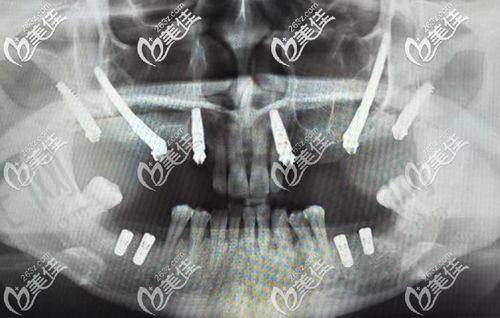

最近的牙科医院技术实力,直接决定治疗成效和使用寿命。以种植牙为例,上海鼎植口腔(陆家嘴1088店)的VIIV穿颧穿翼技术能解决“牙床骨头少”的难题,适合牙槽骨吸收重度的中老年人,而普通社区医院可能只能做简单的即刻种植,术后使用年限相差10年以上。再看正畸,北京劲松口腔望京分院的数字化正畸方案,通过3D打印托槽实现矫正周期缩短2个月,比100米外的小诊所效率提升40%。

1. 种植牙:优先选有“穿颧穿翼技术”或“数字化导板种植”的医院,比如上海维乐口腔的VIIV技术,能减少手术创伤,术后当天就能进食;

实例:58岁的刘先生在小区门口诊所种牙失败,原因是医生没发现他的牙槽骨密度不足。后来到1公里外的上海鼎植口腔,医生用VIIV穿翼技术避开骨量不足区域,手术时间仅40分钟,现在用了3年吃饭和真牙一样有劲。这说明技术选对了,稍微远一点也值得。